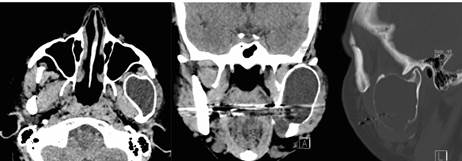

Paciente de sexo mujer, 42 años de edad, con antecedentes de hipotiroidismo en tratamiento, acude al Servicio de Cirugía Oral y Maxilofacial del Hospital San Juan de Dios, en Santiago de Chile, por aumento de volumen hemifacial izquierdo de 6 meses de evolución. Al examen clínico se observó un aumento de volumen de la región parotídea y submandibular izquierda (figura 1), desdentamiento parcial bimaxilar, abombamiento tablas óseas mandibulares y movilidad de tercer molar inferior izquierdo (diente 3.8) (figura 2). La radiografía panorámica reveló extensa lesión en zona posterior del cuerpo y en casi la totalidad de la rama mandibular izquierda, de características quísticas y expansivas, sugerentes de quiste odontogénico (figura 3). En la tomografía axial computarizada (TAC) se observó una lesión de aspecto quístico en la región mandibular izquierda, desde cuello condilar hasta cuerpo mandibular izquierdo, con expansión de corticales óseas vestibular y lingual (figura 4).